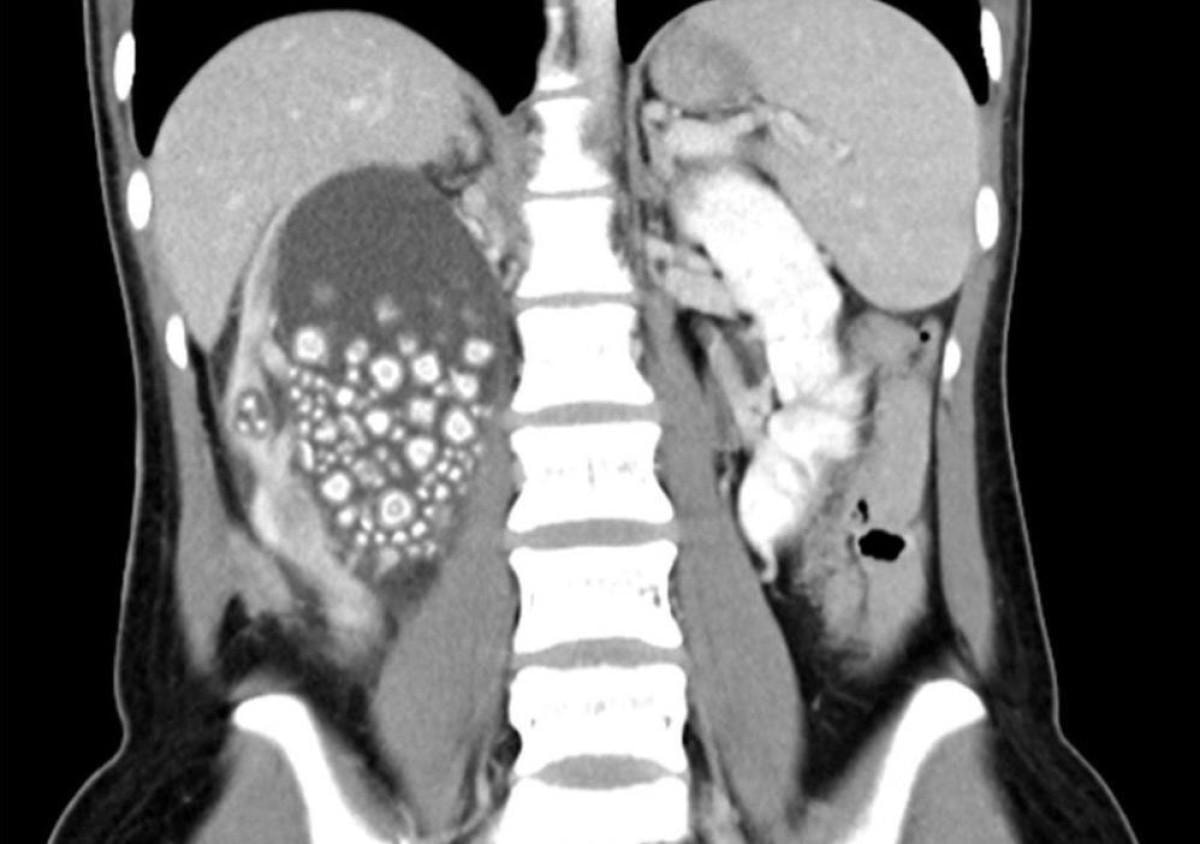

300'den fazla böbrek taşı çıkarıldı

Başarılı geçen ameliyatın ardından Yu’nun böbreklerinden 0.5-2 cm boyutlarında 300’den fazla böbrek taşı çıkarıldı.